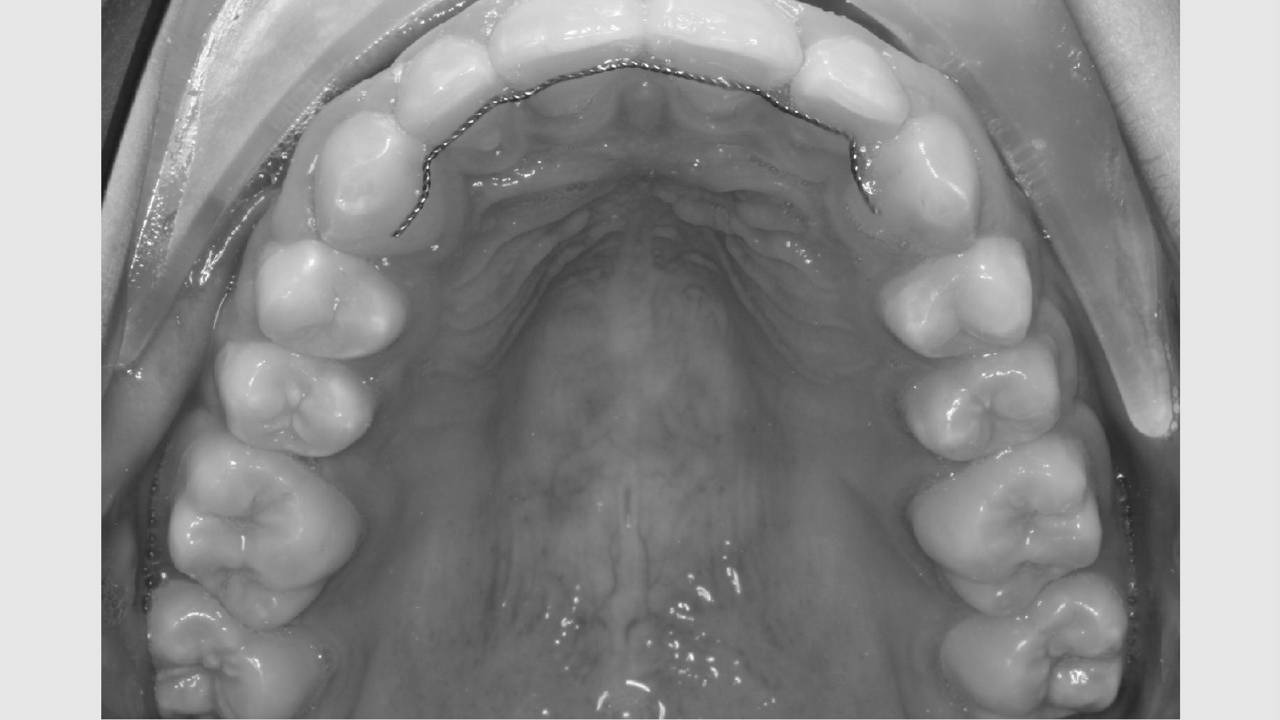

Der bliver taget billeder "udenpå og indeni" samt røntgenbilleder.

Dit barn skal selv holde sine læber til side med en læbeholder, mens tænderne bliver fotograferet. Billederne har følgende formål:

- Der tages røntgenbillede af fortænderne i overkæben som et referencebillede, da disse af og til bliver skadet lidt af en bøjlebehandling. Cirka et halvt år inde i behandlingen bliver der taget ét billede igen som kontrol.